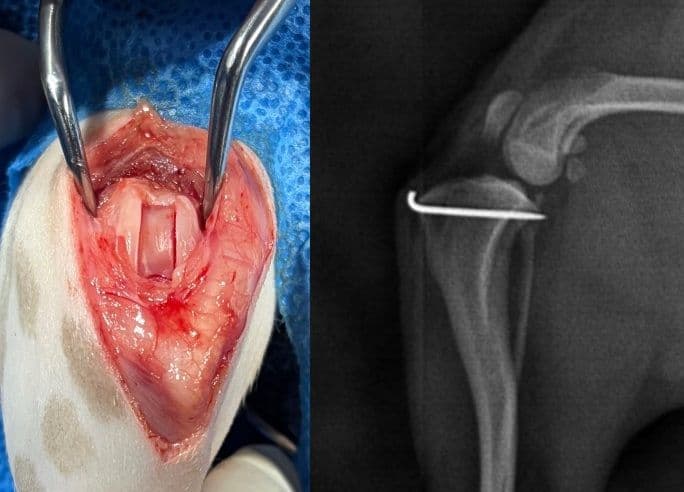

십자인대 수술

TPLO, CBLO, CTWO, 낭외고정술